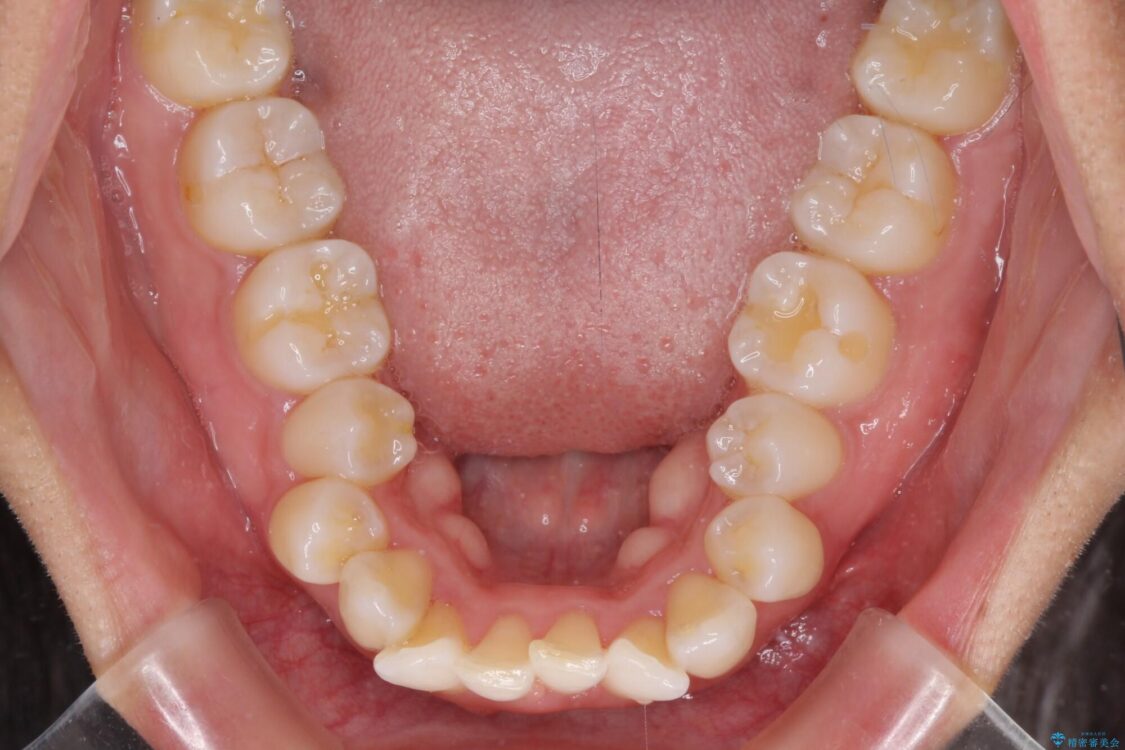

下唇が突き出るような口元の突出感が気になるとのことで来院された患者様です。

上下顎ともに前突した歯列であったので、上下ともに左右の第1小臼歯4本を抜歯し、ワイヤー装置にて矯正治療を行うこととしました。

治療前

• 抜歯矯正で唇を閉じやすく 目立たないワイヤー装置 治療前画像